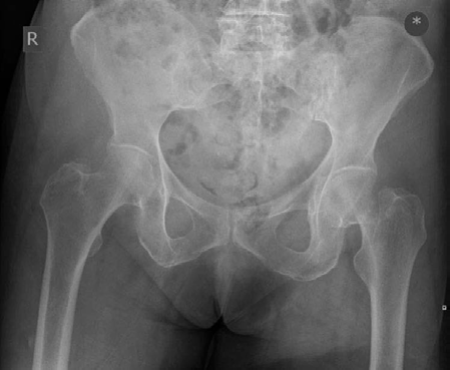

Lower limb Trauma Structured oral examination question 2 A 79-year-old woman fell in her garden sustaining th…